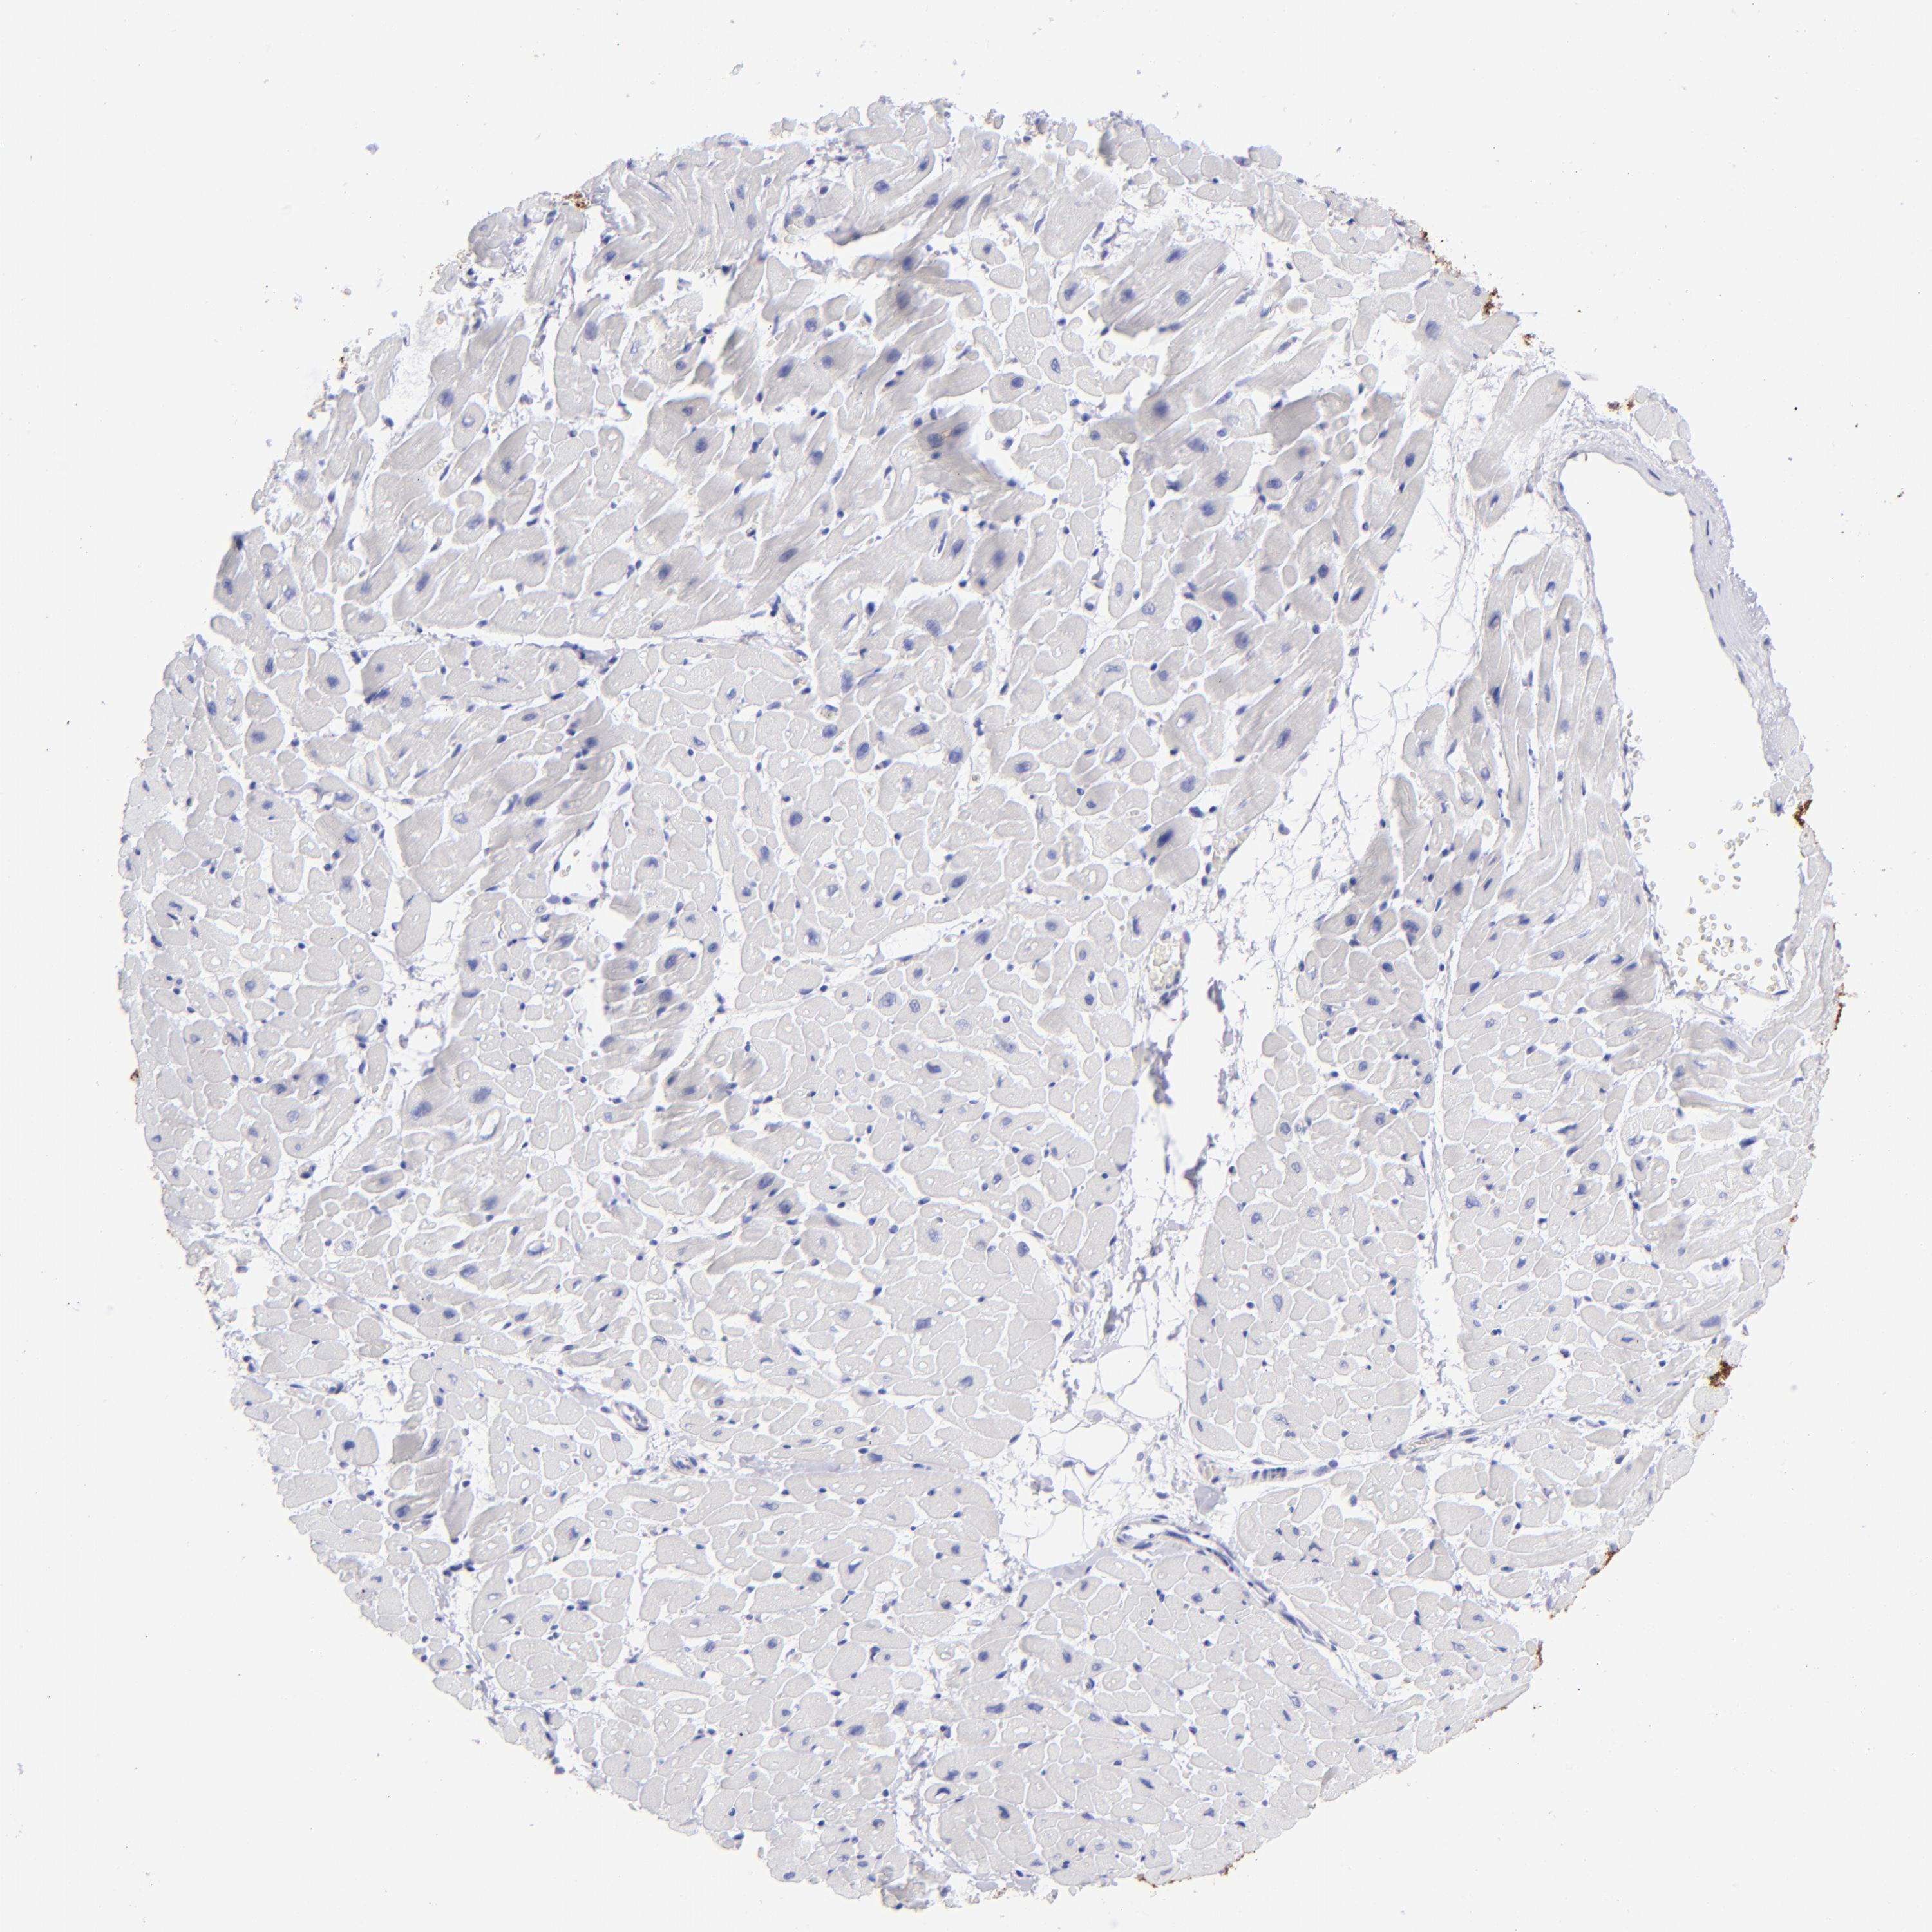

SLC1A3